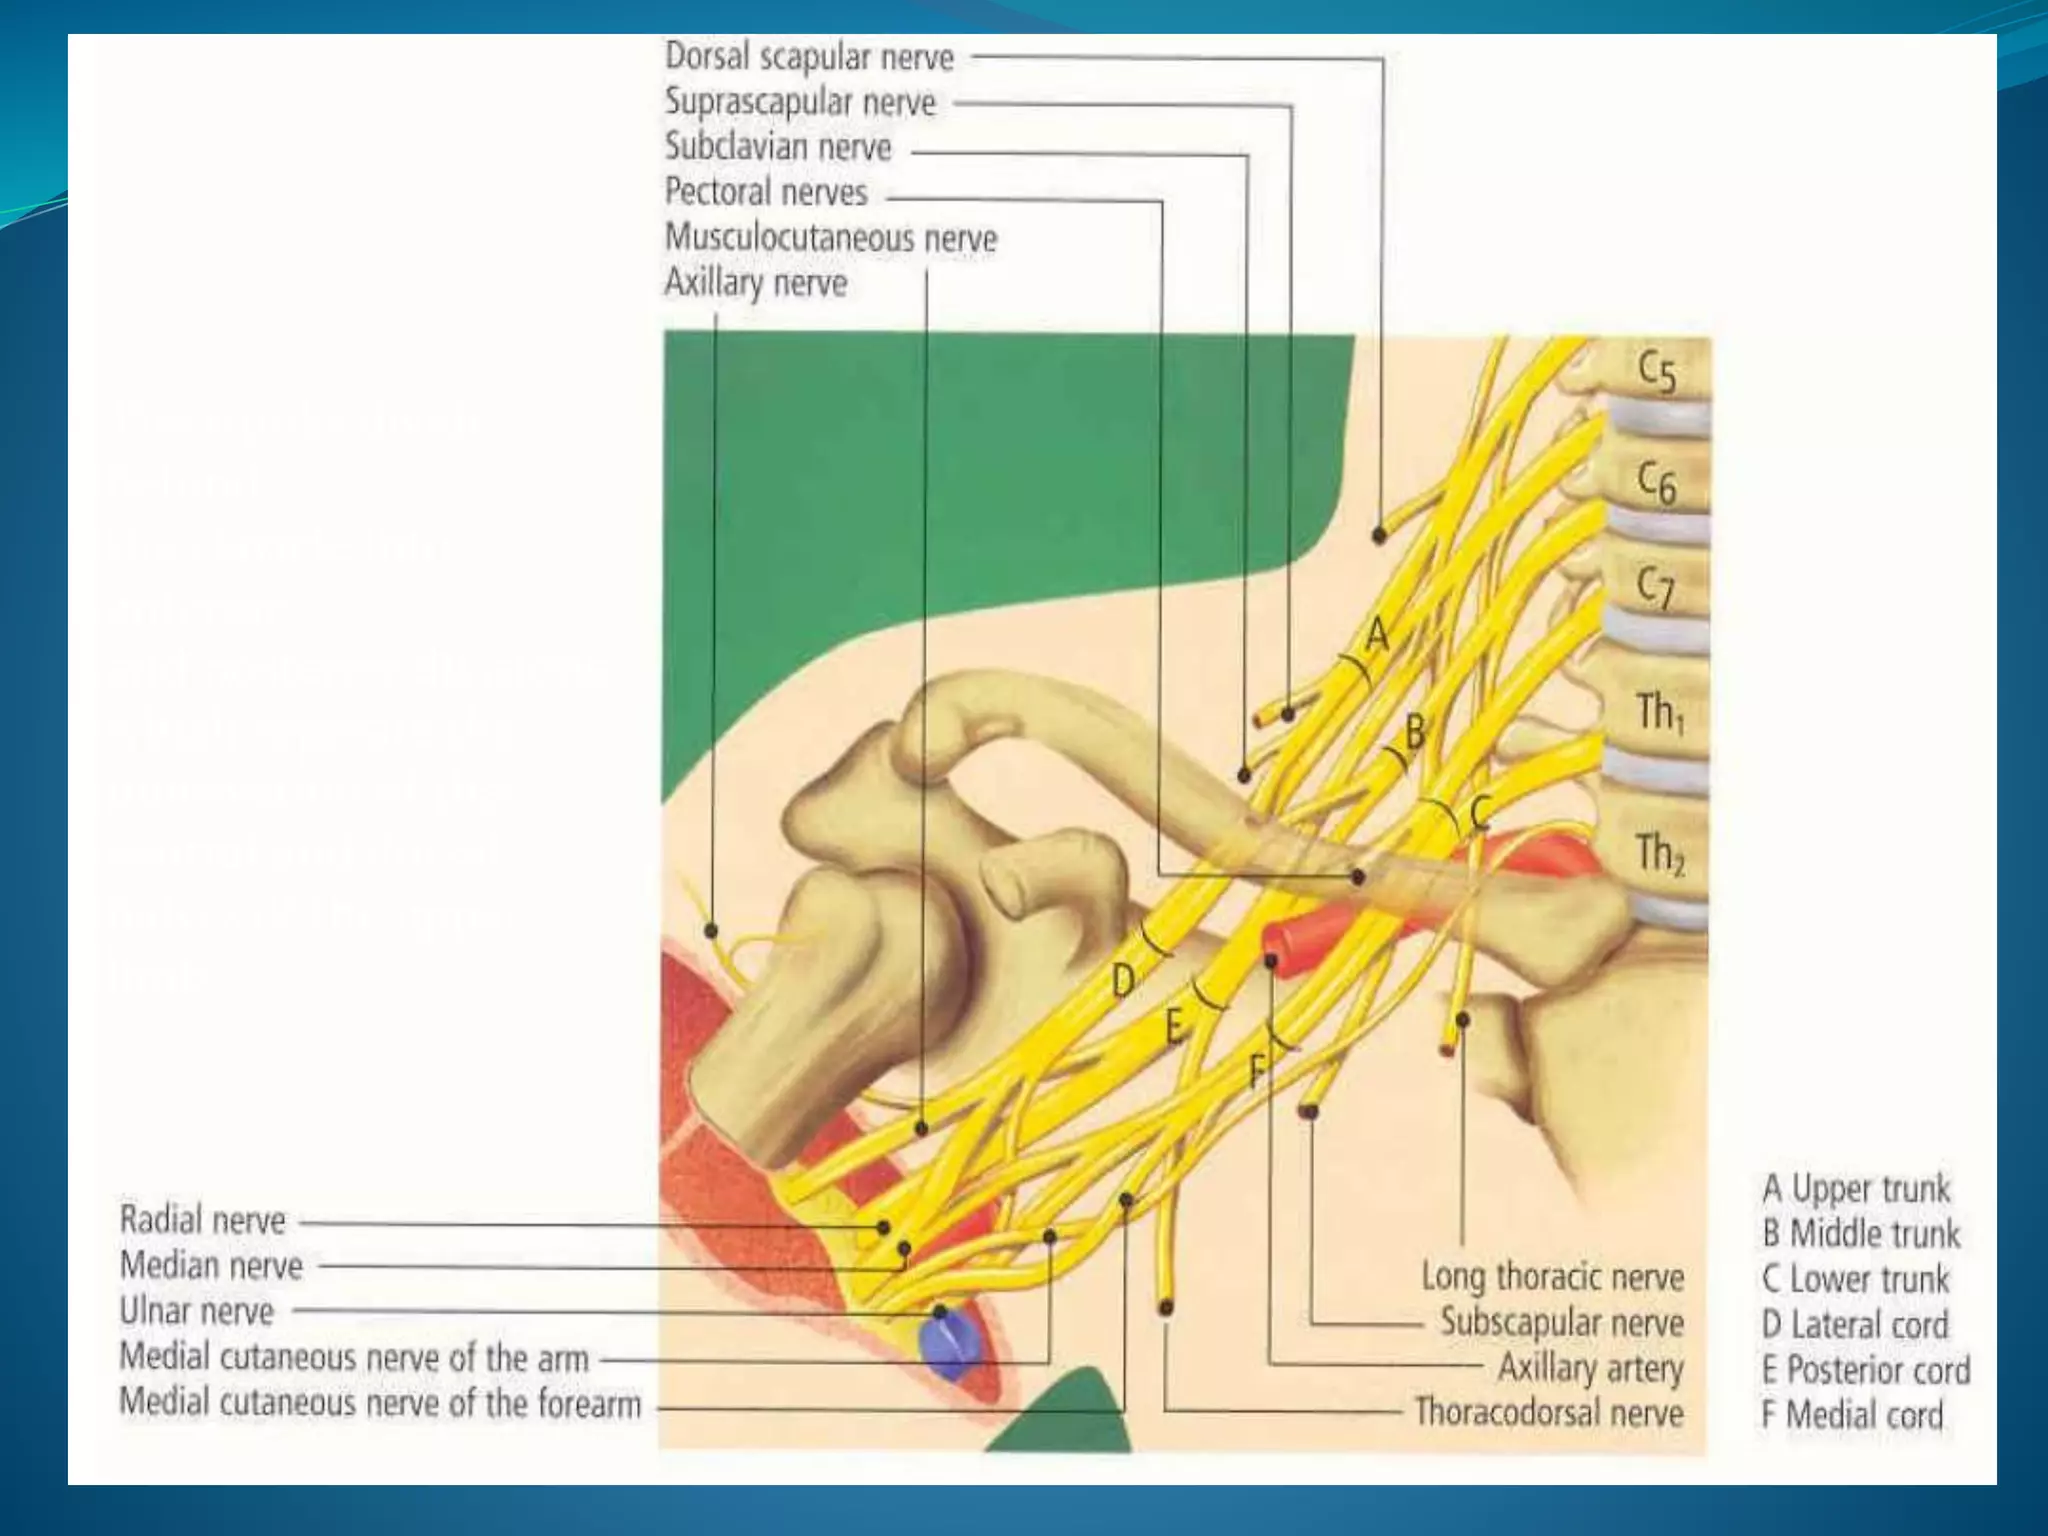

This document provides an overview of brachial plexus anatomy and techniques for brachial plexus nerve blocks. It begins with a description of the brachial plexus formation from cervical and thoracic nerve roots and its branching pattern. Four main approaches for brachial plexus nerve blocks are described: interscalene, supraclavicular, infraclavicular, and axillary. Details are provided on the anatomy and techniques for performing interscalene and supraclavicular brachial plexus blocks. Ultrasound guidance is discussed as an advancement which allows real-time visualization of needle and nerve. Complications are also summarized.